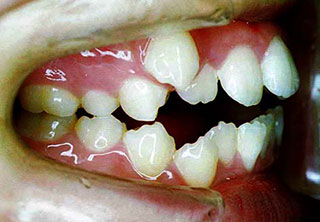

![]() |

⑨舌小帯拘縮症(短縮症):舌小帯(舌の裏のヒモ)が短いと、舌の運動が十分にできないので発音・嚥下機能だけでなく、歯列の成長を妨げ、結果このような重度の叢生となります。 |